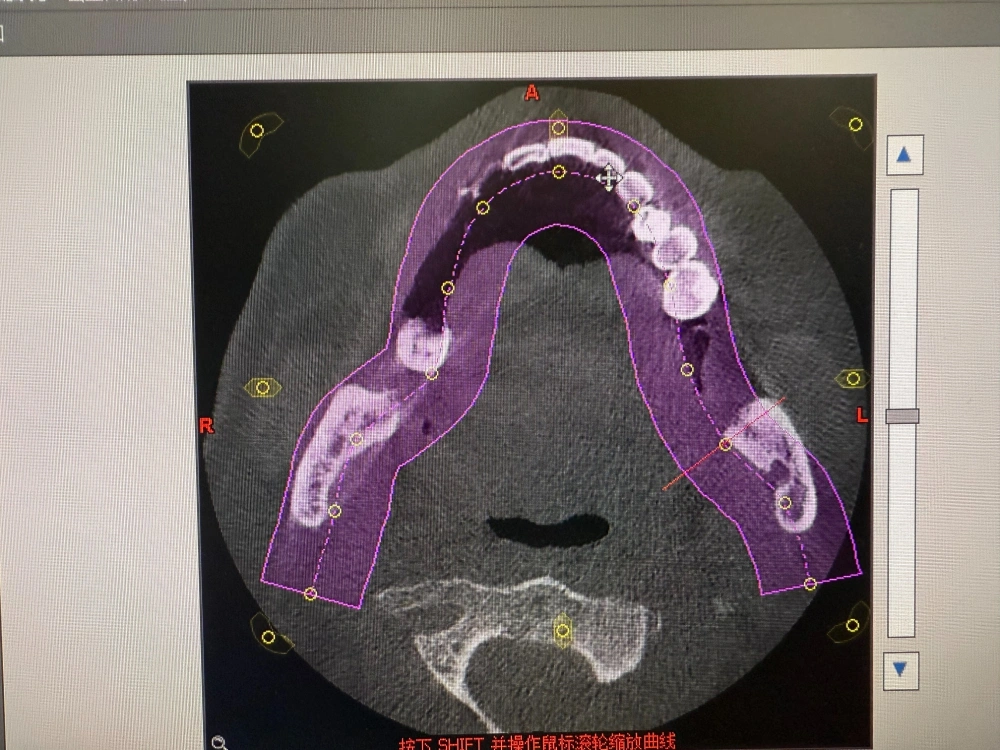

我是当事人的女儿,我父亲今年77岁了,事发前他刚从海南回东北跟我们子女在一起聚聚,他当时有四颗坏掉的牙想尽快根治。7月16日,他看到了哈尔滨市优诺口腔的宣传小广告后一个人去医院咨询,本来想治牙,结果医院建议我父亲把下部的牙全部拔掉后种牙,还说种完牙后吃麻麻香,但现在从片子上来看完全没必要这样做。事发后我们询问了其他口腔医院的医生,所有的医生都说拔牙要评估病人的身体,以我爸高血压、糖尿病、冠心病还有5个心脏支架这种情况,他们可能连拔牙都不会,更不用说一次性拔12颗,甚至还种了6颗,这个破坏是非常大的,正常人可能都受不了,全国都没有这样的案例。

7月17日做手术那天是我陪着去的,我们去得时候开开心心的,我特意跟主治医生说明了我父亲的身体情况,当时医生说没有问题,他拔牙什么的不影响,很有把握,因为他是那家医院的副院长,我们就完全相信他了。这个手术据工作人员说给我们打了5折一共是2万多,原先要4万多,做得是口腔的局部麻醉,但因为手术室是封闭的,不让家属去,一开始不知道手术的具体情况。直到我们后期看了当时手术的监控视频,才发现手术有那么多的问题。

最大的问题是主刀医生,最开始说是由副院长给我父亲进行手术,但实际上并不是他,是一个助理医师给做的。手术全程一个半小时,副院长只在手术室里待了9分钟,9分钟内他把牙钉种在了牙床上,就干了这么一件事,后续带帽、缝合等系列操作全是助理医师独立完成。 种牙是要有资格的,由一名不具备独立操作资格的助理医师实施高风险的手术,属于“非法行医”,整个手术他们存在太多问题了。